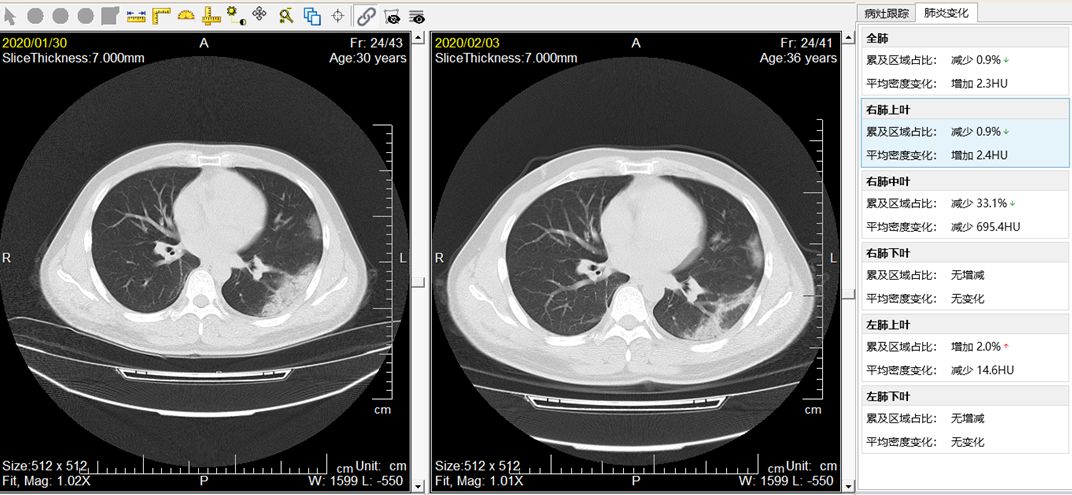

2月12日,零氪科技研发的“新型冠状病毒性肺炎智能辅助诊断系统”,在河南驻马店平舆县人民医院完成部署并第一时间投入使用,系统根据胸部CT影像数据,应用前沿的人工智能算法,判别患者新冠肺炎阳性几率,并给出辅助诊断报告,具体包含肺炎病变识别、肺炎病变分析、病情进展评估,以及根据检测及分析结果自动生成检测报告等功能模块,帮助医生更快速、更准确的完成新型冠状病毒性肺炎的筛查与诊断,为当前超负荷工作的医生节省精力与时间,同时降低患者等待时间,减少交叉感染风险。

疫情期间,零氪向各级医疗机构免费提供这套系统服务,目前已经在天津、河南、云南、福建等多地投入部署,临床检出率达到90%以上,极大地缓解了基层临床医生的压力。

新型冠状病毒肺炎只能辅助诊断系统